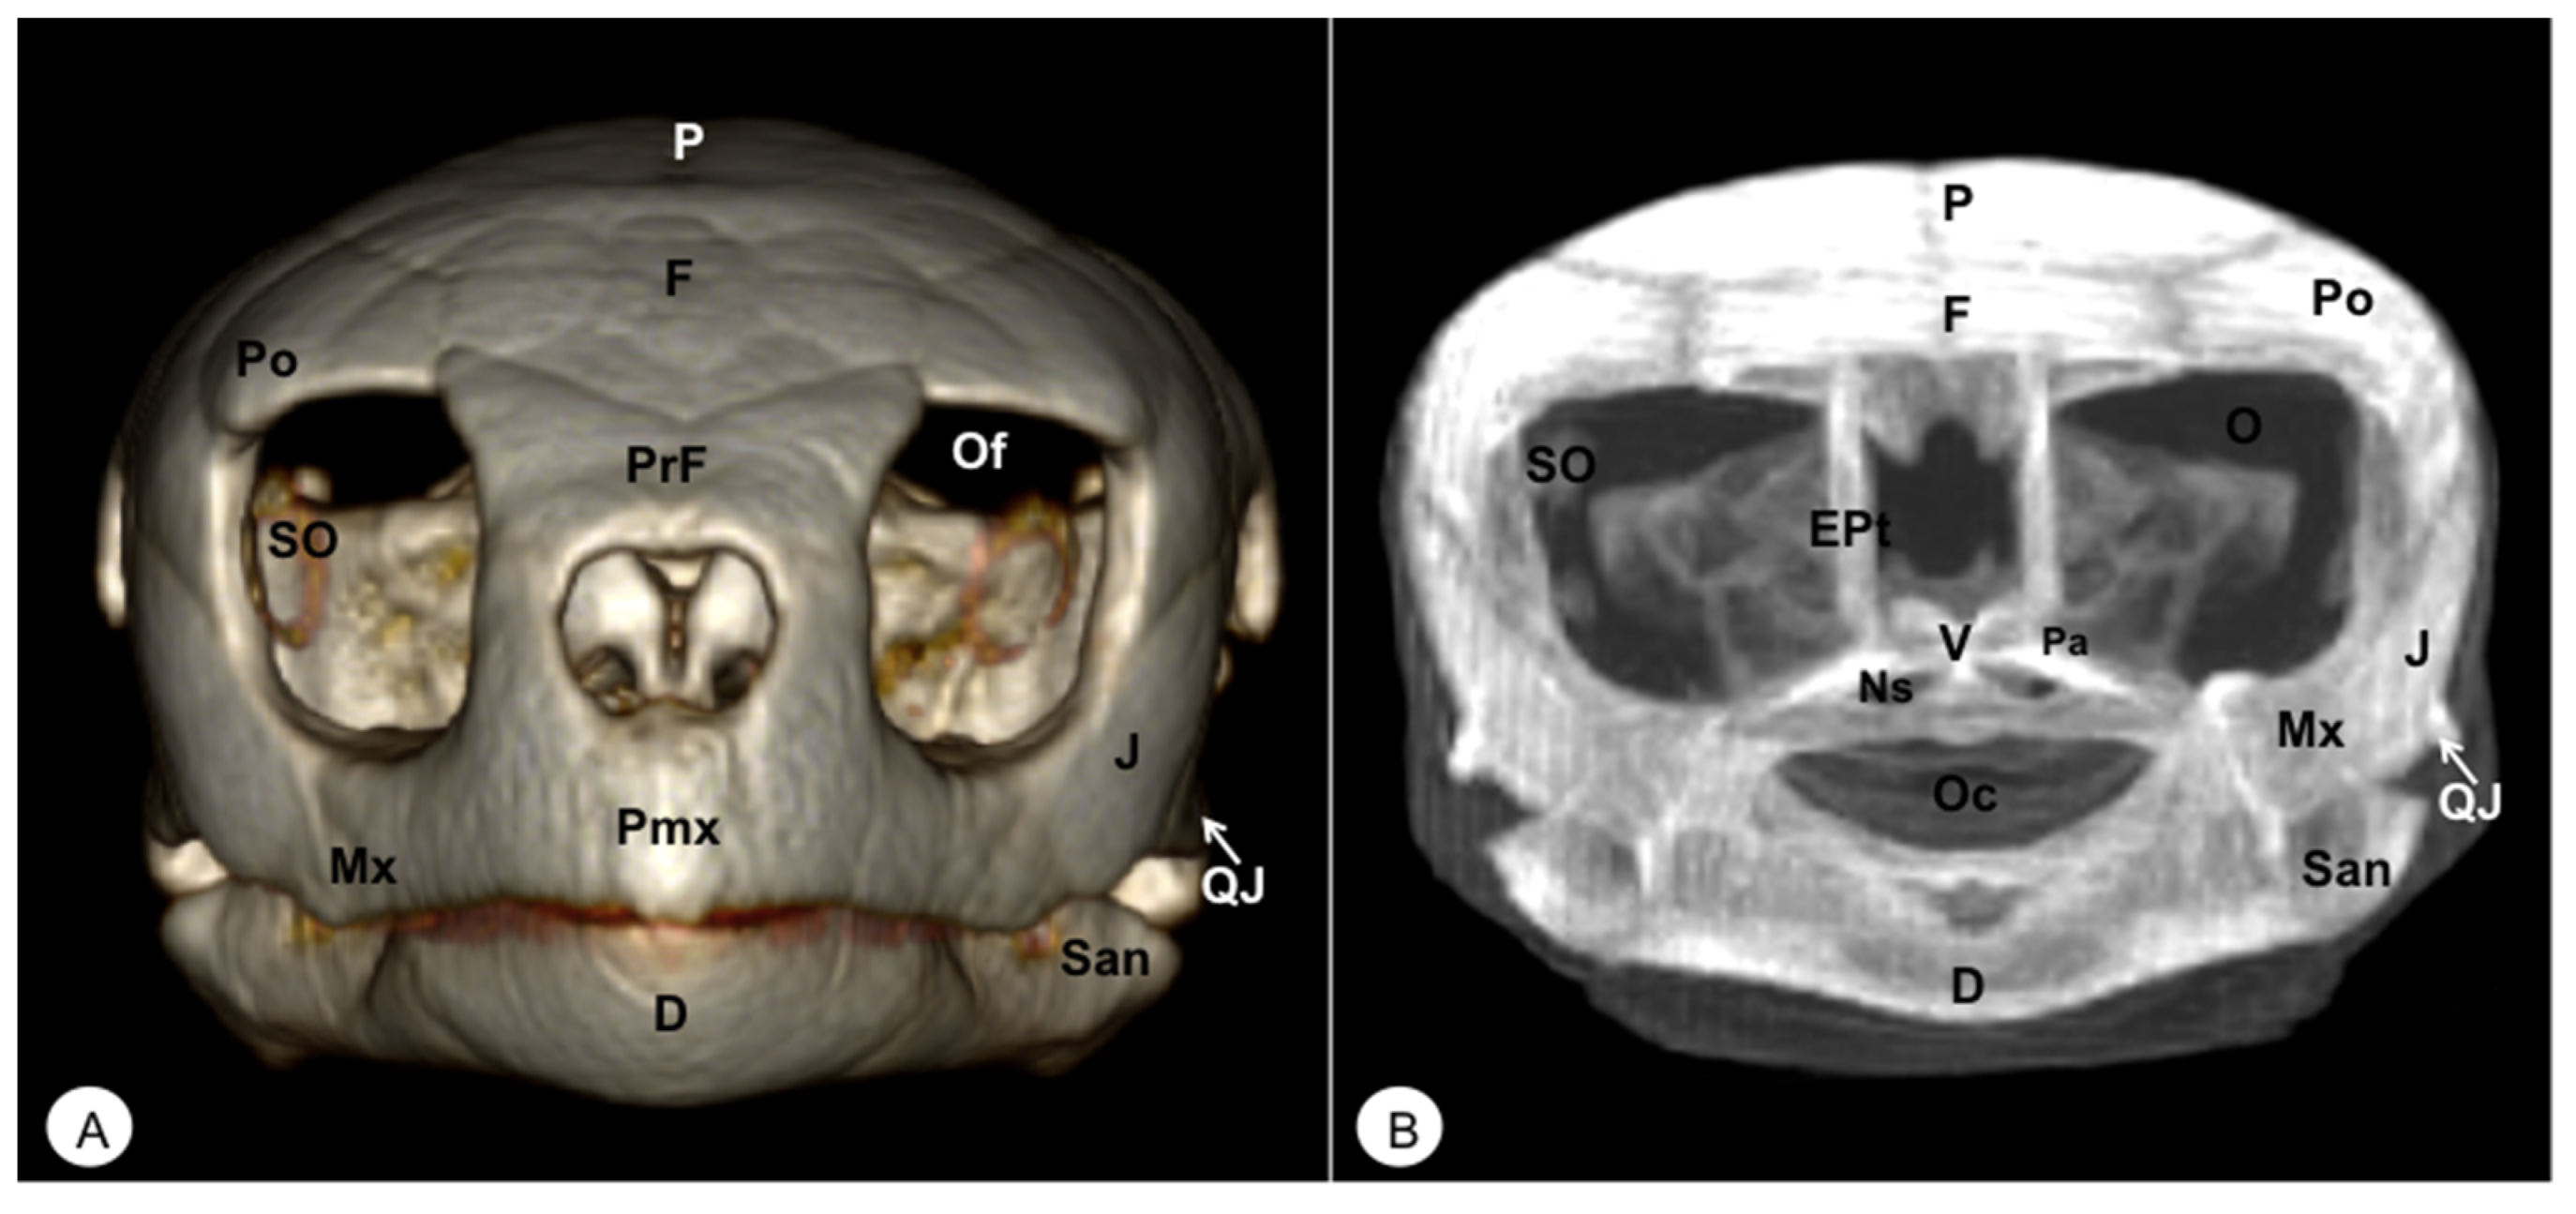

Figure 2. Head of Caretta caretta. (A) Rostral VR image. (B) Rostrotransversal MIP image. Pmx: Premaxillary bone. PrF: Prefrontal bone. F: Frontal bone. Po: Postorbital bone. O: Orbit. Of: Orbital fossa. J: Jugal bone. QJ: Quadratojugal. Mx: Maxillary bone. SO: Scleral ossifications. P: Parietal bone. EPt: Epipterygoid bone. V: Vomer. Pa: Palatine bone. Ns: Nasal sinuses. Oc: Oral cavity. D: Dentary. San: Surangular.

The premaxillary bones are narrow, showing a V shape. These bones are the most rostral bony structures of the turtle head (Figure 2A and Figure 3, Figure 4 and Figure 5). Its rostral VR image showed the absence of dorsomedial processes in these bones, allowing the joining of the nostrils (nares) at the midline. This paired bone articulates laterally with the maxillary bone (Figure 2A, Figure 3, Figure 4 and Figure 5A) and caudoventrally with the anterior end of the vomer (Figure 4). We distinguished a similar configuration in the iguana, where it comprises a tooth-bearing alveolar plate. This bone contacts the nasal bone dorsally (Figure 7, Figure 8 and Figure 10), the maxilla caudolaterally (Figure 7, Figure 8 and Figure 10), and the vomer caudomedially (Figure 10B).

3.1.2. MAXILLA (Os Maxillare)

3.1.6. PREFRONTAL-FRONTAL

In these species, the frontal bone shows a flat shape and lies in the anterior part of the skull (Figure 2, Figure 3, Figure 5, Figure 7, Figure 8 and Figure 10). The rostral VR turtle reconstruction showed a clear view of the prefrontal and frontal bone junctions (caudomedially). Therefore, the frontal bone contacts the prefrontal bone (rostrally), the postorbital bone (laterally), and the parietal bone (caudally) (Figure 2, Figure 3 and Figure 5). As our animals were adults, we could observe how this bone was excluded from the orbit. The VR and MIP images of the green iguana showed that the prefrontal bone contacts rostromedially with the nasal bone, rostrolaterally with the lacrimal bone (paired small bones located in the lateral region of the orbit observed only in the iguana), and caudomedially with the frontal bone (Figure 7, Figure 8 and Figure 10). The frontal bone is broad and forms a major component of the skull roof, contributing to the dorsal border of the orbit. It meets the prefrontal bone rostrolaterally, the postfrontal bone caudolaterally, and the parietal bone caudally (Figure 7, Figure 8 and Figure 10). Laterally, it is differentiated from the postorbital by the postfrontal bone.

3.1.7. POSTFRONTAL-POSTORBITAL

The postorbital bone forms part of the temporal arch, and most of the posterior margin of the orbit. This bone contacts dorsocaudally with the parietal bone, anterodorsally with the prefrontal bone, and ventrally with the jugal bone (Figure 2, Figure 3 and Figure 5), excluding, therefore, the frontal bone from the orbit. It reaches the squamosal caudally (Figure 3A and Figure 5) and contacts the prefrontal bone rostrally (Figure 2A, Figure 3A and Figure 5). Regarding the iguana, those bones were broad and could be well identified in VR and MIP rostral, dorsal, and lateral images as two different bones. The postfrontal bone arises in the caudodorsal part of the orbit and meets the frontal bone (rostromedially), the parietal bone (caudomedially), and the postorbital bone (caudolaterally) (Figure 7, Figure 8 and Figure 10). In contrast, the postorbital bone meets the postfrontal bone dorsally, the squamosal bone caudolaterally, and the jugal bone rostrolaterally (Figure 8 and Figure 10).

3.1.9. JUGAL (Os Jugale)

The jugal bone is one of the main elements of the zygomatic arch under the orbit in both species, showing an “L” shaped configuration in VR and MIP lateral images. Rostral and lateral VR images were quite useful in distinguishing the arrangement of this bone at the caudoventral border of the orbit. Moreover, the rostral, lateral, and ventral VR and MIP images of the turtle show how this bone contacts dorsocaudally with the postorbital bone, rostrally with the maxilla, and posteriorly with the quadratojugal bone (resulting in the zygomatic arch). In contrast, the jugal bone in the iguana is observed as a curved bone (seen by rostral, lateral, and dorsal VR and MIP images) that runs forward along the orbital border to make contact with the lacrimal (dorsally) and maxillary bones rostrally. Caudodorsally, it angles slightly upwards to meet with the postorbital and the squamosal bones. Ventrally, it contacts the ectopterygoid bone.